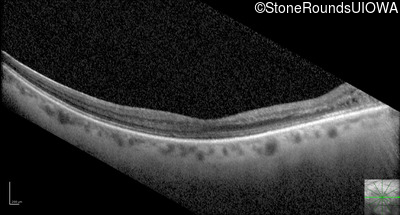

Optical Coherence Tomography - Right - 20/100 +1

Exemplar / OCT Stack

OCT Stack